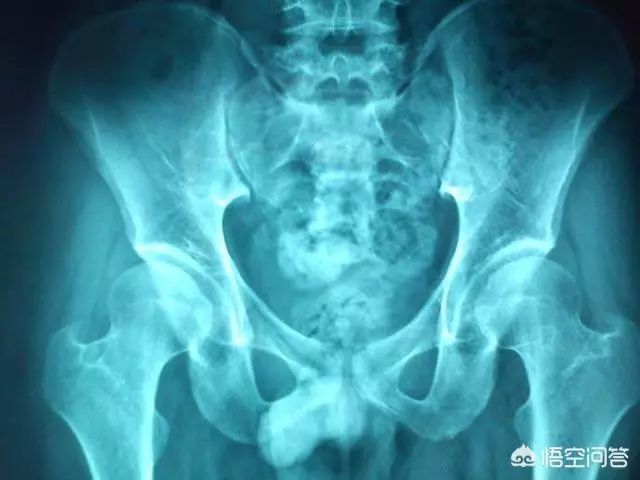

发现类似问题,应该请教专业儿童骨科医生同时也许要通过B超或X光检查协助诊断。

如果大腿纹不对称,做什么检查呢?

自我检查是存在漏洞的!如果条件允许建议及时去医院拍片然后找专业医生进行判断!!